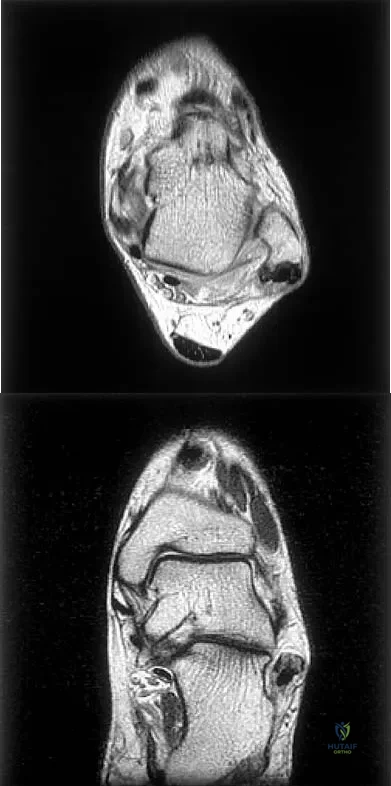

Figures 5a and 5b show axial and coronal MRI images of the left ankle of a patient with lateral ankle pain. What is the most likely diagnosis?